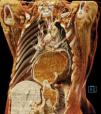

A 70-year-old woman had a past medical history of mixed large and small cell neuroendocrine carcinoma, with a focal component of endometrial adenocarcinoma that metastasized to the lung, as well as a history of a large hiatal hernia (>5 cm) (Fig. 1). She was admitted to the emergency department due to oppressive chest pain, radiating into the neck, that was exacerbated with food intake. Laboratory work-up reported leukocytes 21.3 × 109/L, neutrophils 18.3 × 109/L, C-reactive protein 37.8 mg/dL, lactate dehydrogenase (LDH) 241 IU/L, and lactate 2.7 mmol/L. Cardiac evaluation showed no alterations and angiotomography was negative for pulmonary thromboembolism but revealed an “hourglass” hiatal hernia (Fig. 2). Decompression was carried out with a nasogastric tube, and due to suspected gastric strangulation, the patient underwent hiatal hernia reduction and laparoscopic gastropexy, resulting in pain improvement. Hiatal hernias are divided into four types, the most complex of which are the paraesophageal hernias (types III and IV), accounting for 5–10% of cases (Fig. 3). In addition to the stomach, this type of hernia can contain parts of other abdominal viscera, such as the colon, small bowel, pancreas, or spleen. Acute complications of strangulation or ischemia warrant immediate decompression.